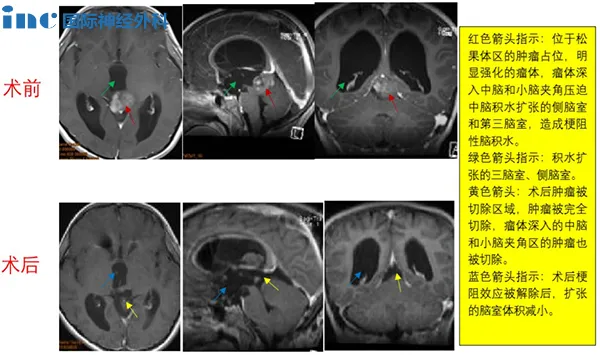

CASE 5:8岁男孩-松果体肿瘤

病史摘要:8岁男童出现头痛、眼球运动障碍等症状,经磁共振检查结果为“松果体区占位合并幕上梗阻性脑积水”。脑脊液分流加辅助放化疗半年后,早期症状并无好转。巴教授最终顺利全切。

手术过程:术中,患者俯卧位,后正中头皮切口,经幕上、幕下联合入路,最终肿瘤得以全切除,且尽力减少了组织的损伤,对预防后期肿瘤的复发起到了极大作用。

术后情况:术后第一天患者清醒,术后ICU观察两天,术后一般情况好,无明显并发症,顺利出院。患儿的各种症状全都消失,恢复了正常机体功能,近期复查时肿瘤也并无增长。